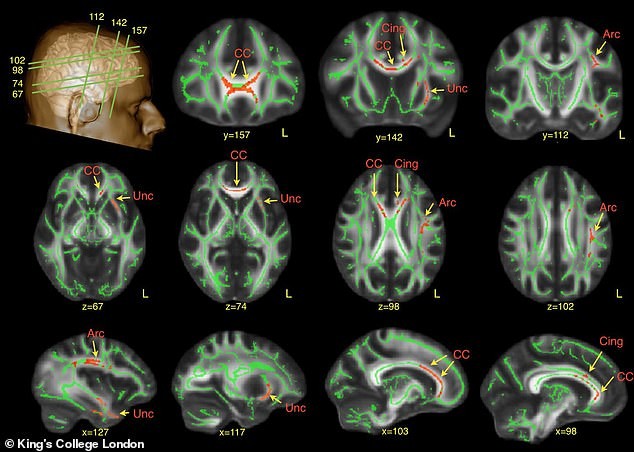

Денес не постои лек што директно го третира аутизмот, но одредени медикаменти помагаат за справување со анксиозност, импулсивност и проблеми со спиењето. Дополнителни немедицински пристапи, како когнитивно-бихејвиорална терапија, говорна терапија, диета, нутриционистичка поддршка и тренинг на социјални вештини се исто така важни. Мозоците на аутистични лица имаат суптилни разлики, посебно во региони поврзани со јазик и препознавање лица.